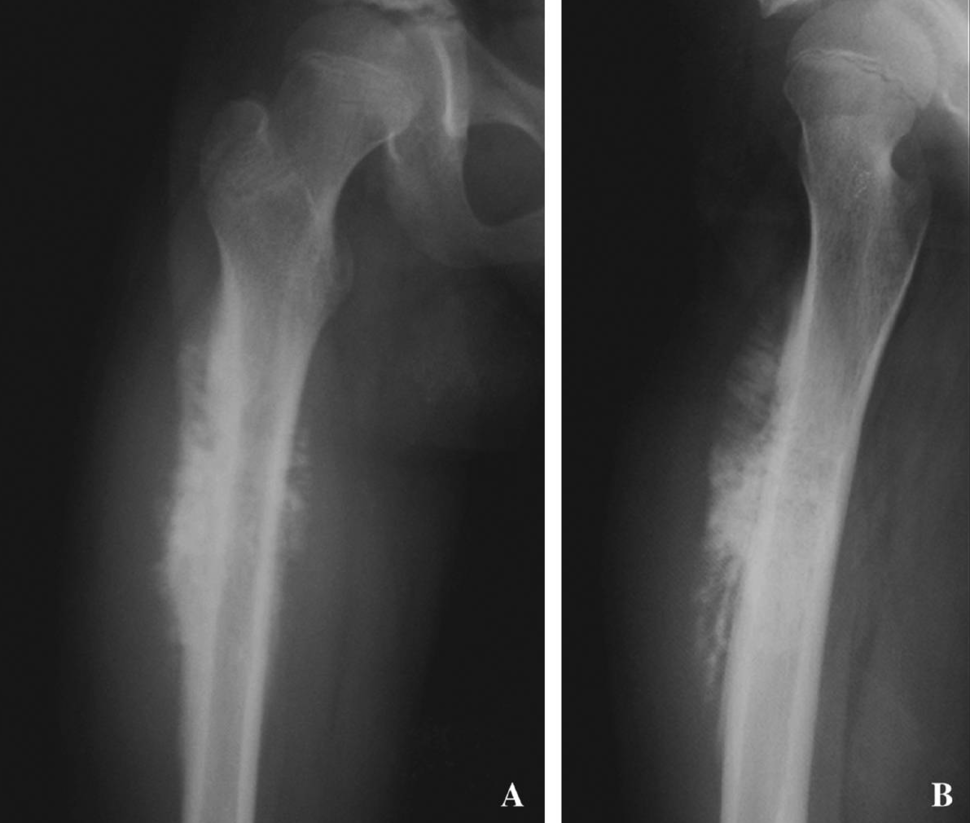

An x-ray of a femur (thigh bone) from a patient with osteosarcoma.

Credit: Ups J Med Sci. 2009 Dec; 114(4): 249–255. doi: 10.3109/03009730903177340 (CC BY 2.5)